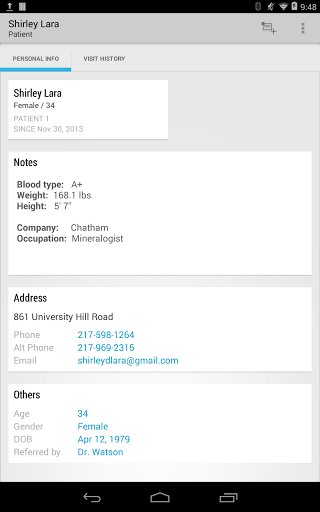

• Obtenir des informations patient directement à partir de vos contacts téléphoniques

• Personnalisez les informations patient que vous souhaitez capturer

• Voir la visite du patient / antécédents médicaux